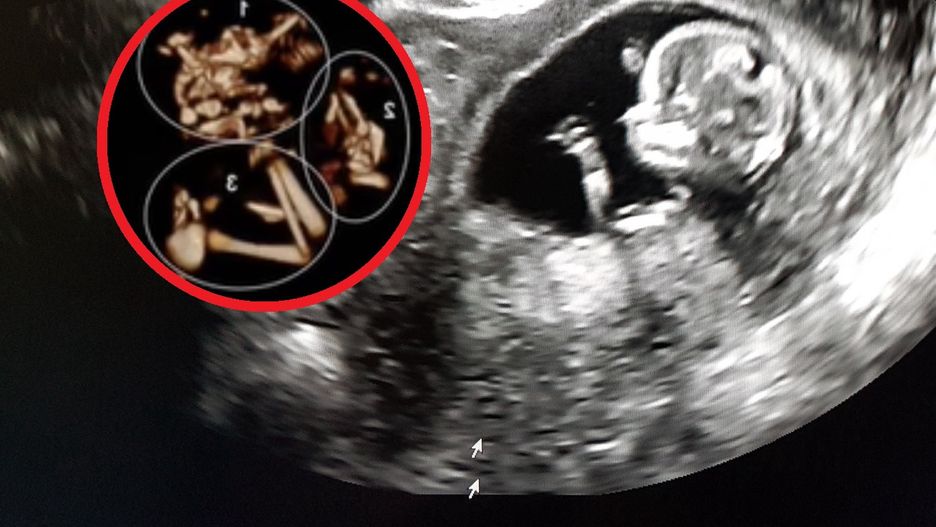

Płód w 8 tygodniu ciąży (bliźniaki)

Ekspert szczegółowo tłumaczy w filmie opublikowanym na platformach społecznościowych na czym polega to zjawisko i jakie ryzyko z nim się wiąże. Widać wyraźnie na zdjęciu z USG ślady kończyn drugiego płodu w głowie dziecka.